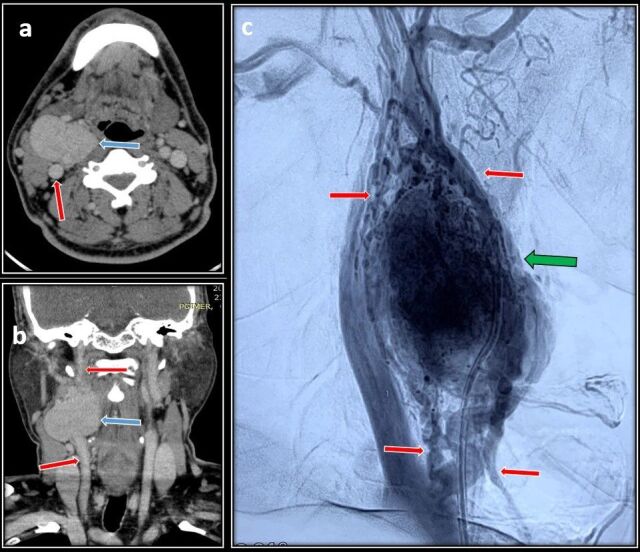

A 47-year-old male presented with a right-sided Shamblin type 2 carotid body tumor measuring 5*5 cm. After preoperative embolization, a sub adventitial resection of the tumor was done. He was discharged after postoperative day 5 and presented again to emergency 10 days later with a bleeding pseudoaneurysm at the surgical site causing dysphagia and dyspnea. He was taken for emergency exploration of the surgical wound and, intraoperatively, it was observed that the proximal ends of the internal carotid artery and external carotid artery close to the bifurcation were forming a pseudoaneurysm, 1 cm distal to the common carotid artery. The external carotid artery was ligated and a common carotid to internal carotid artery bypass was done with a reversed saphenous vein graft. He recovered well in the postoperative period and was discharged on day 7. Pseudoaneurysm formation following carotid body tumor resection is extremely rare and has only been reported thrice in the literature.

Abstract Image